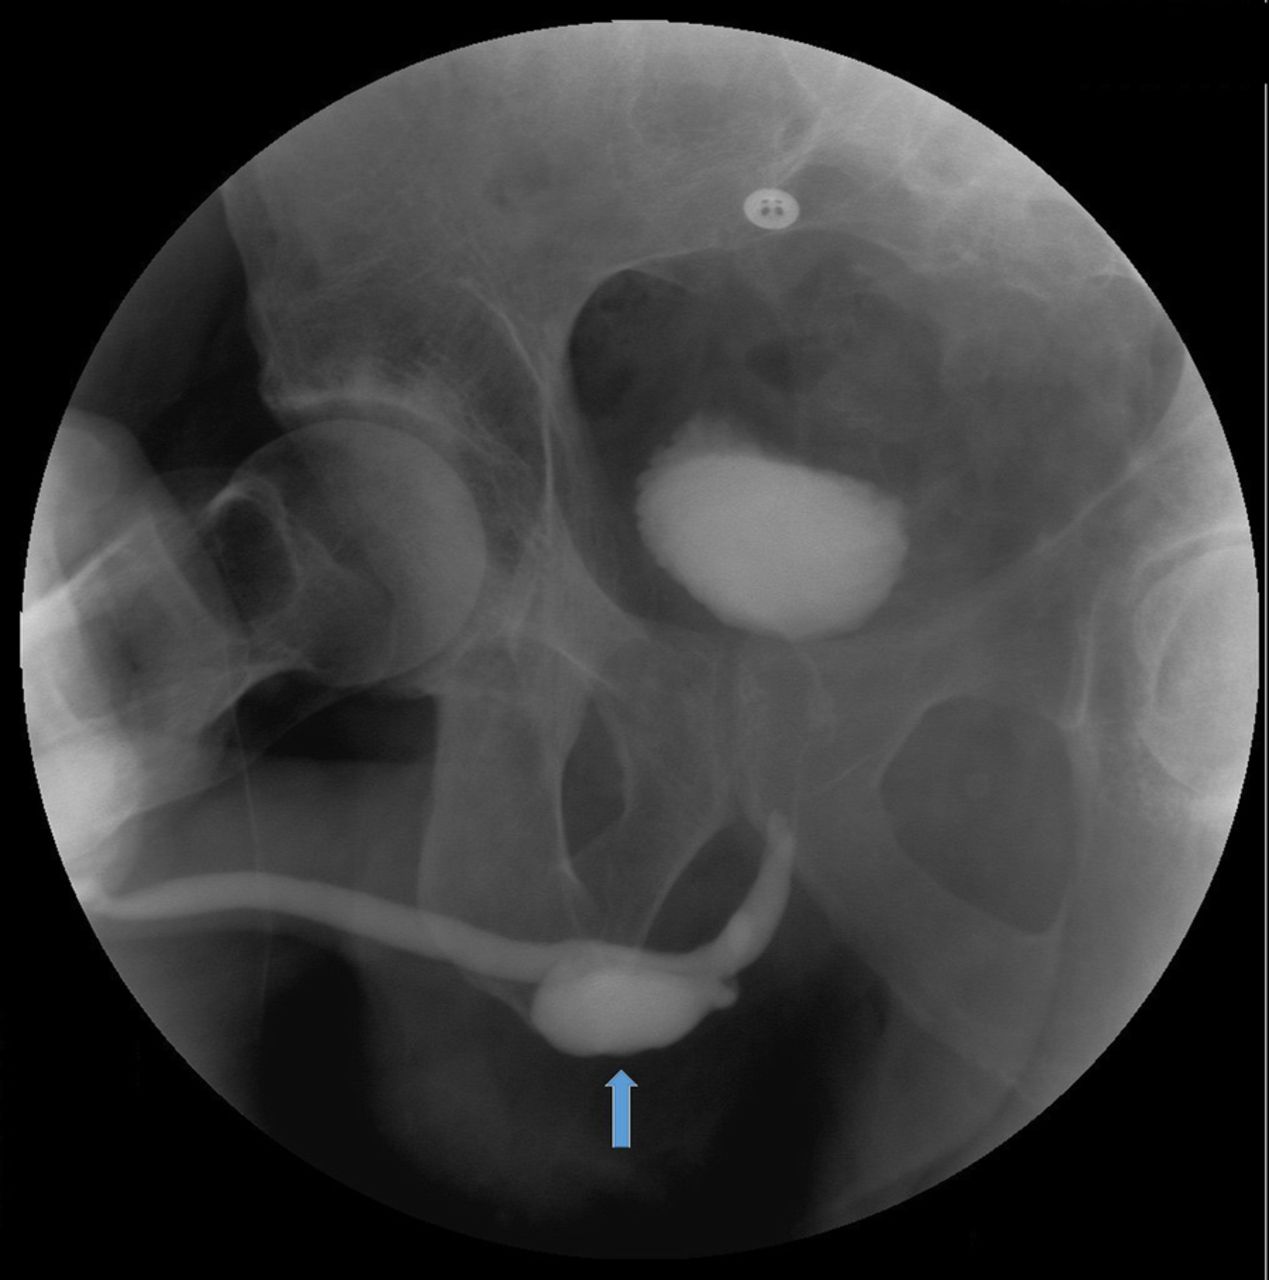

Discover what a persistent right umbilical vein (PRUV) means for fetal development. This guide explains the clinical significance of this vascular anomaly, how it is detected via prenatal ultrasound, and what expectant parents need to know about follow-up monitoring and long-term outcomes to ensure a healthy pregnancy journey.

Read full article: Persistent Right Umbilical Vein